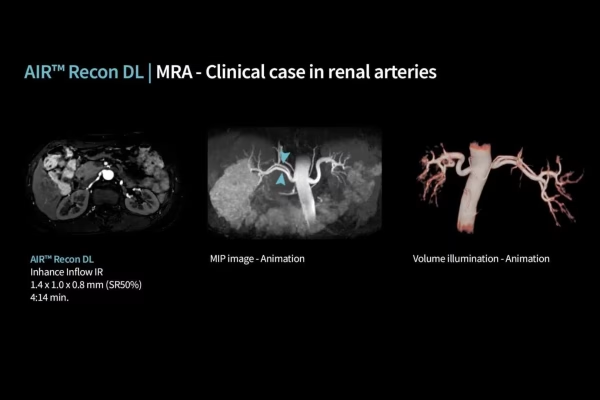

IRM GE Signa Explorer 1.5T